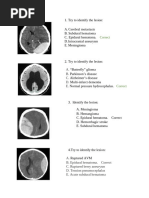

450) Papilledema presents with transient vision loss associated with changes in head position and is secondary to increased